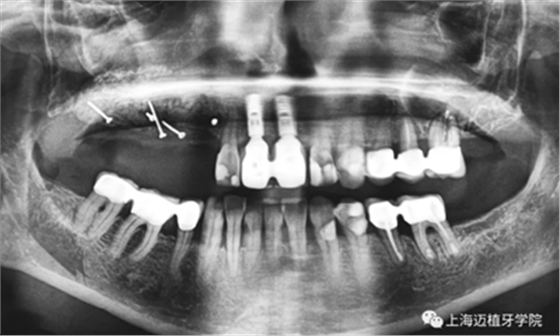

術前照,生物骨材料植骨失敗,植體暴露,生物骨材料沒有成骨(如圖),垂直向和水平向都受到感染

GBR骨生物材料植骨失敗后,利用BBA植骨法及軟組織處理病例

植體取出后,可以清晰地看到骨粉未成骨,還是顆粒狀

處理程序